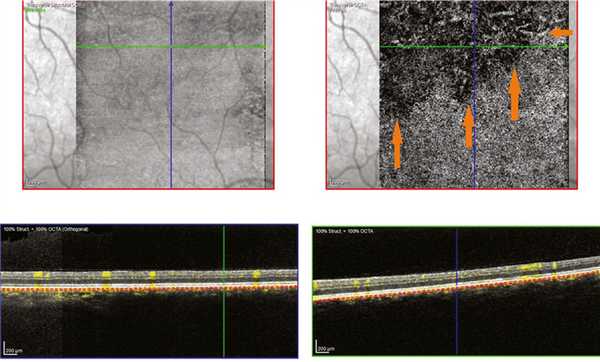

Визуализация склеро-хориоидального сочленения на левом глазу была возможна только в режиме исследования в глубине тканей (EDI). Было выявлено расширение хориоидеи до 815 мкм субфовеолярно и 872 мкм парафовеолярно снаружи в первую очередь за счет расширения наружных слоев хориоидеи. Данные изменения в большей степени были выражены кверху от фовеа (рис. 4, а, Рис. 4. Результат ОКТ. Срезы через фовеа: левого глаза — горизонтальный (а), вертикальный (б); правого глаза — горизонтальный (в). б).

В режиме ОКТ-ангио выявлено изменение структуры хориоидеи выше фовеа — отмечено уменьшение плотности хориокапилляров и крупных сосудов хориоидеи (рис. 5). Рис. 5. Результат ОКТ-ангиографии. Срез на уровне хориокапилляров через фовеа правого (а) и левого (б) глаза. Зона обеднения сосудистого рисунка указана стрелками.

Аналогичная картина отмечена и в парафовеолярной зоне — в верхней половине выявлено обеднение хориоидального сосудистого рисунка на уровне хориокапилляров, что, с нашей точки зрения, может свидетельствовать о замедлении кровотока в расширенных сосудах хориоидеи (рис. 6). Рис. 6. Результат ОКТ-ангиографии левого глаза. Срез на уровне хориокапилляров парафовеолярно сверху. Зона обеднения сосудистого рисунка указана стрелками.